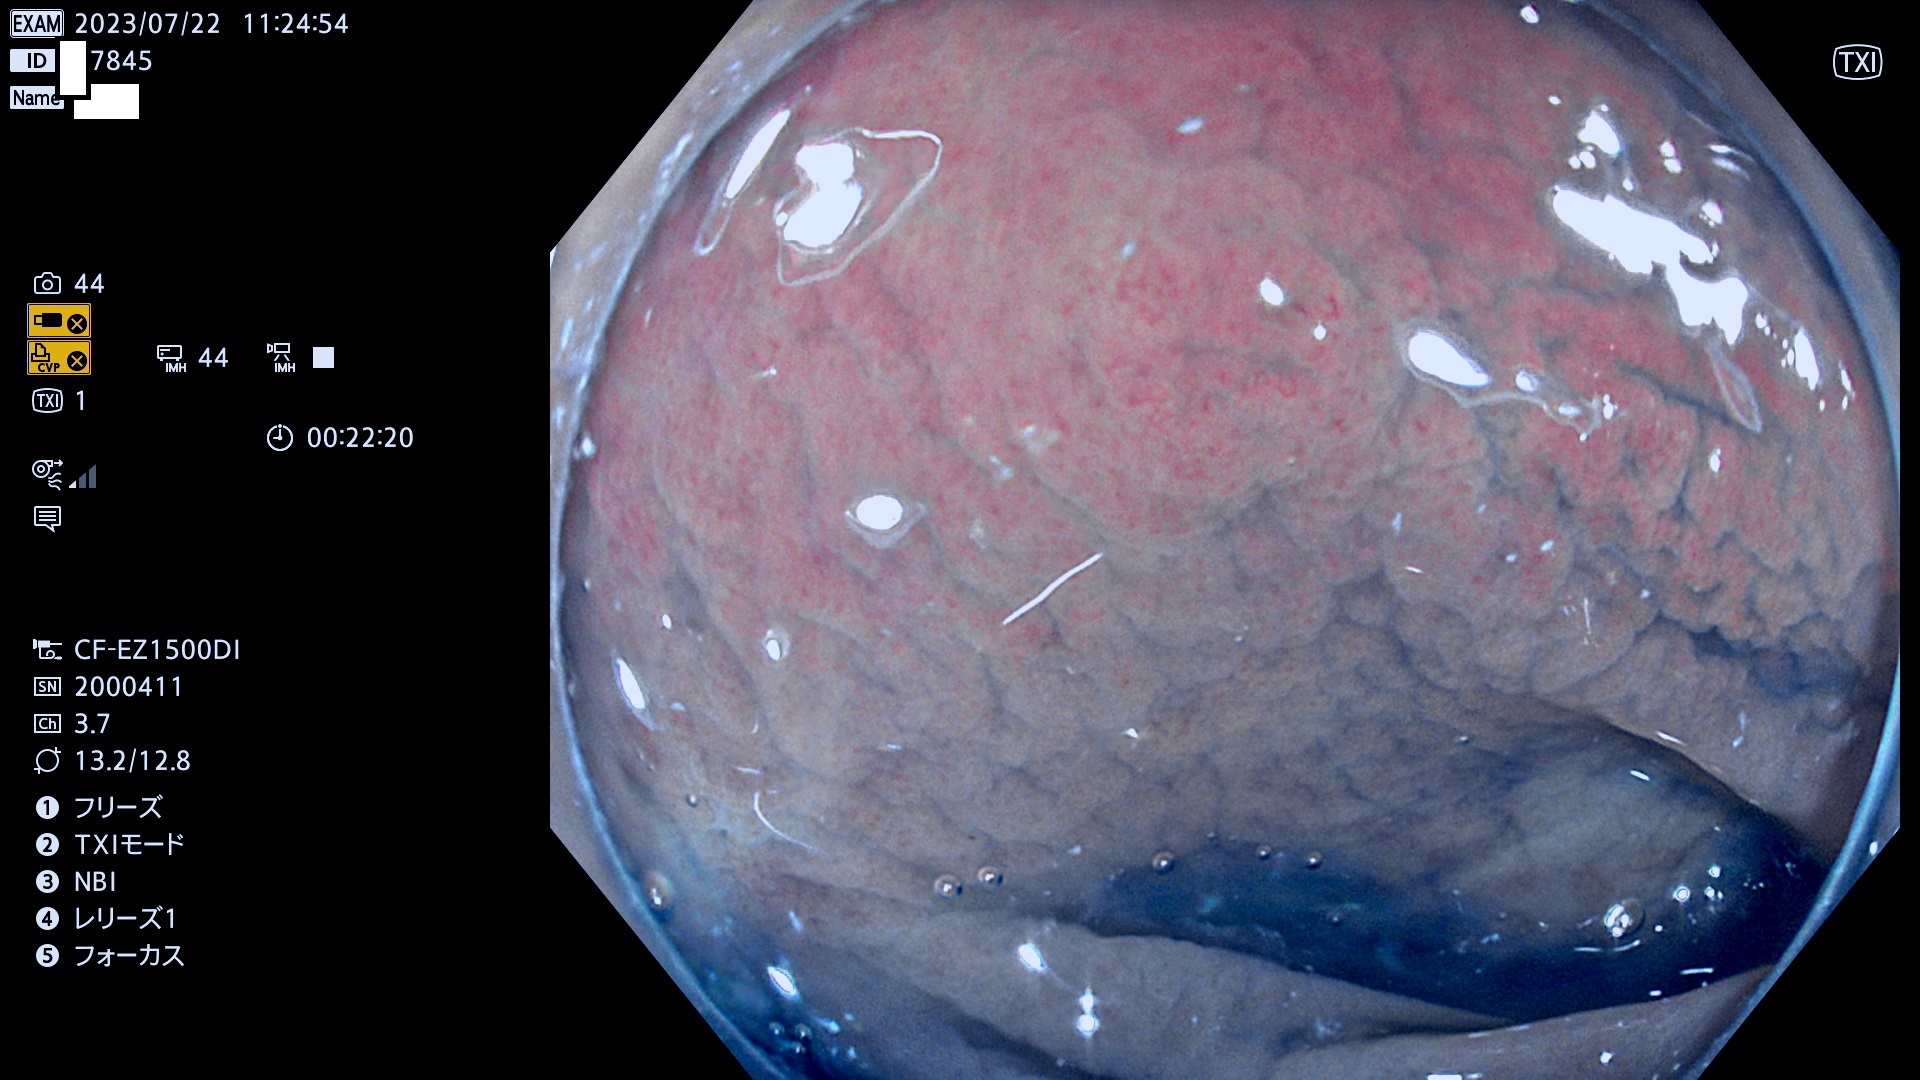

「表面型腺腫(Flat Adenoma)の中で、完全に平坦な物をUb、陥凹している物をUcと呼びます。平坦隆起型(Ua)よりも、発見が難しく危険な病変です。このタイプは「内視鏡後・大腸癌の重要犯人」であり、この発見率は「腺腫発見率」よりも、重要な意味があります。

抽出の対象期間 2023年7月20日(木)〜7月23(日)の4日間(48件の検査)12件